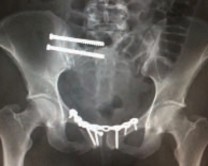

Рис. 2. Рентгенограмма пациента после операции

Окончательная фиксация переломов таза выполнялась нашим пациентам в отсроченном порядке, на 10-14 сут, после устойчивой адаптации организма к новым условиям, в двух случаях оперативное вмешательство выполнено на вторые сутки после травмы [5, 6]. Всем пациентам выполнена открытая репозиция, фиксация тазового кольца тазовыми пластинами А.О. фирмы Synthez, 32 пациентам выполнена инверсия аппарата внешней фиксации на погружные конструкции [6]. В после операционном периоде пациенты получали антикоагулянтную, антибактериальную терапию, инфузионную терапию. ЛФК под контролем инструктора начинали с 3 суток после операции [7].